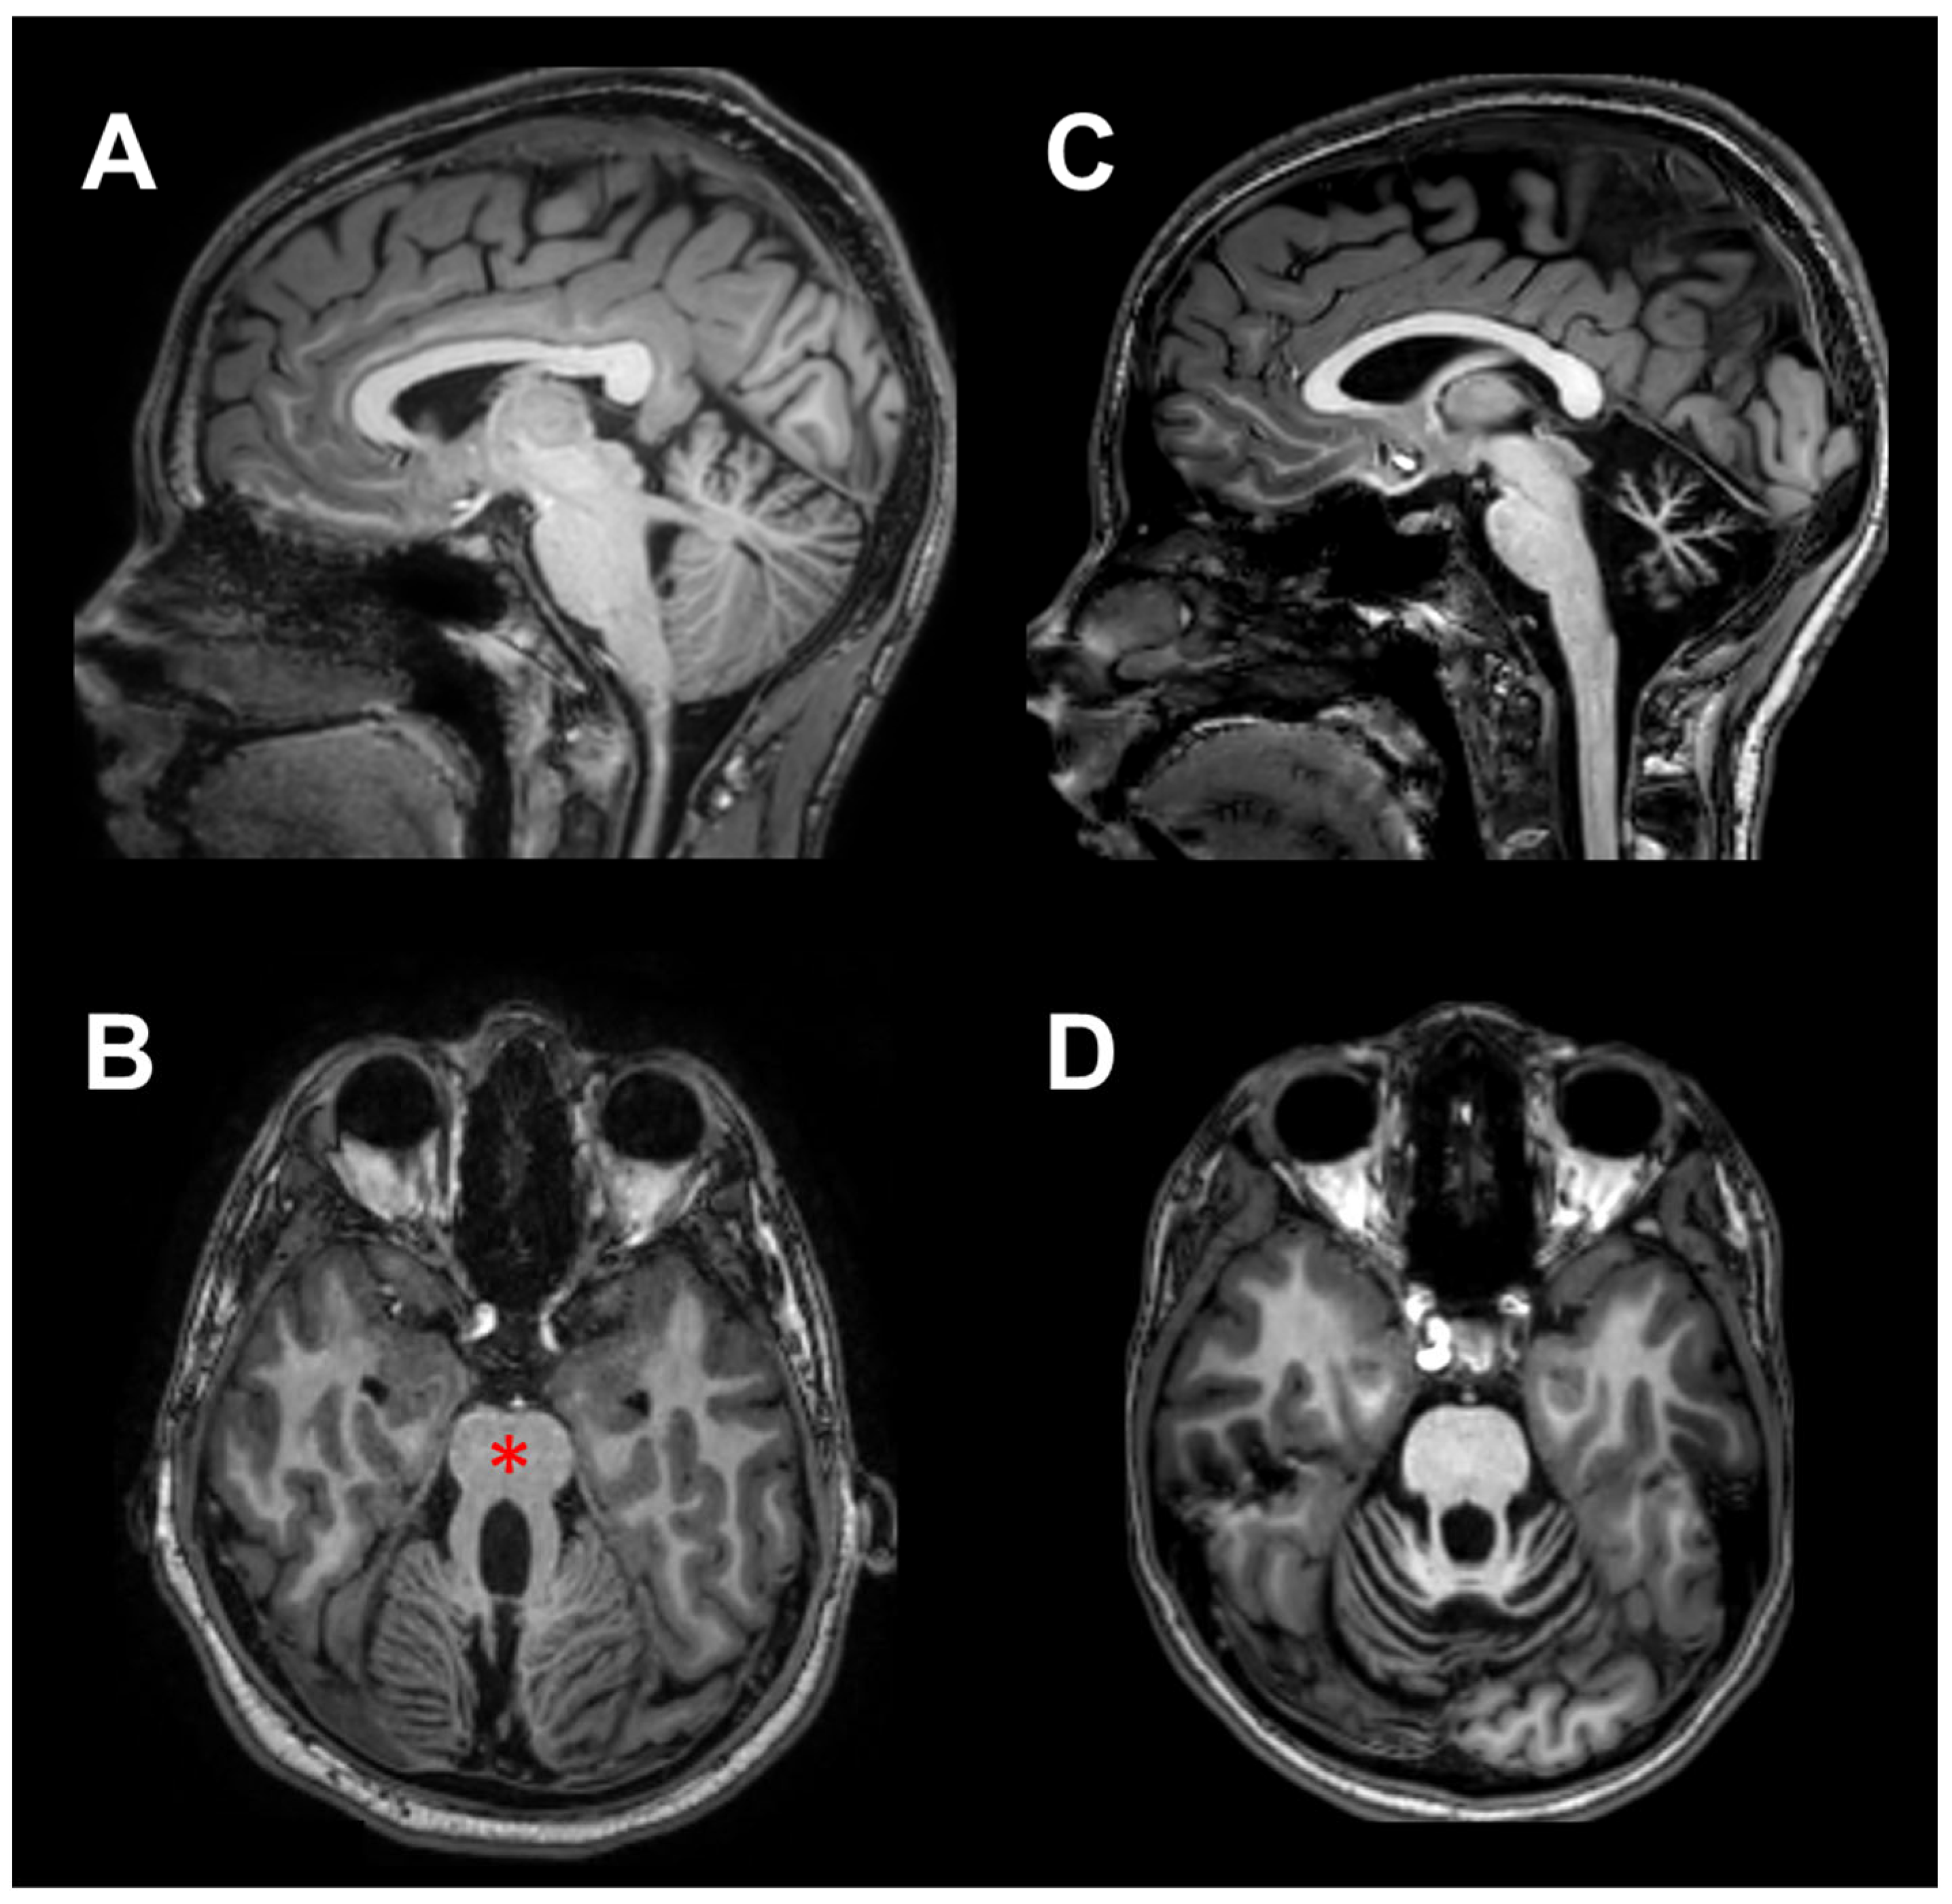

- Farinelli, V.; Palmisano, C.; Marchese, S.M.; Strano, C.M.M.; D’Arrigo, S.; Pantaleoni, C.; Ardissone, A.; Nardocci, N.; Esposti, R.; Cavallari, P. Postural Control in Children with Cerebellar Ataxia. Appl. Sci. 2020, 10, 1606. [Google Scholar] [CrossRef]

- Romani, M.; Micalizzi, A.; Valente, E.M. Joubert Syndrome: Congenital Cerebellar Ataxia with the Molar Tooth. Lancet Neurol. 2013, 12, 894–905. [Google Scholar] [CrossRef] [PubMed]